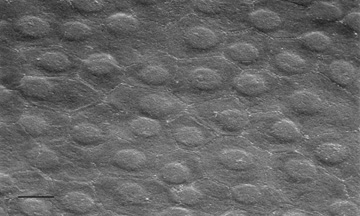

Having a sufficient number of endothelial cells to cover the posterior surface of the cornea along with having integrity of their cell junctions (tight and gap junctions), which are present in the intercellular spaces between endothelial cells, establishes the barrier function of endothelium (Figs. 12 and 22, 23, and 24). Clinically, the barrier function of the cornea can be assessed in vivo by the use of specular microscopy or confocal microscopy (endothelial cell density) or fluorophotometry (permability). In healthy human eyes, this barrier prevents the bulk flow of fluid from the aqueous humor to the corneal stroma, but does allow moderate diffusion of nutrients, water, and other metabolites to cross into the stroma through the 20 nm wide intercellular space. This leaky endothelial barrier may initially seem inefficient, but when one considers that most nutrients for all layers of the cornea come from the aqueous humor, the situation is reasonable.

Fig. 23. Scanning electron micrograph (1,000×) on the posterior surface of the corneal endothelium from a 65-year-old patient with healthy eyes. Note how the hexagonal endothelial cells form a uniform monolayer. Bar = 10 μm.